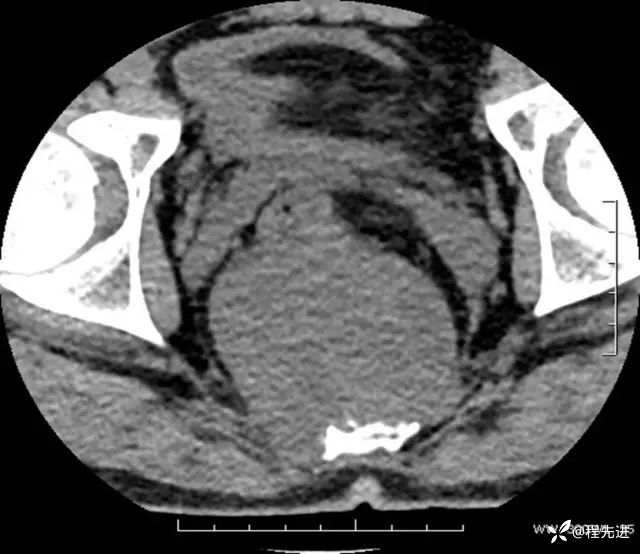

CT平扫:

软组织窗: